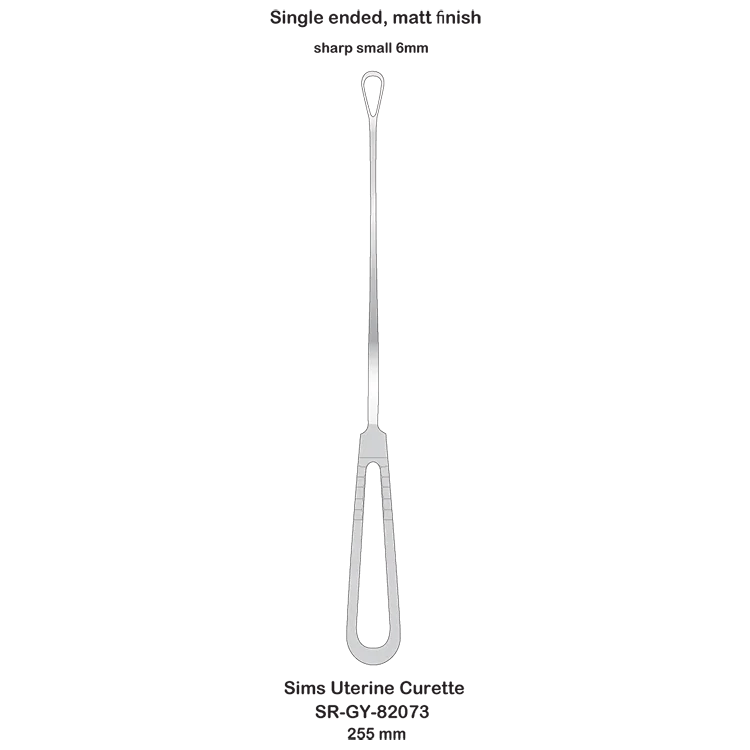

Sims Uterine Curette gynecological obstetric high quality surgical instruments

- Category:

- Supplier: SURGI,RANGE,CORPORATION

In Stock